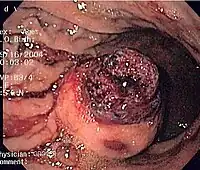

Small GISTs

Since GISTs arise from the bowel layer called muscularis propria (which is deeper to the mucosa and submucosa from a luminal perspective), small GIST imaging usually suggest a submucosal process or a mass within the bowel wall. In barium swallow studies, these GISTs most commonly present with smooth borders forming right or obtuse angles with the nearby bowel wall, as seen with any other intramural mass. The mucosal surface is usually intact except for areas of ulceration, which are generally present in 50% of GISTs. Ulcerations fill with barium causing a bull's eye or target lesion appearance. In contrast-enhanced CT, small GISTs are seen as smooth, sharply defined intramural masses with homogeneous attenuation.